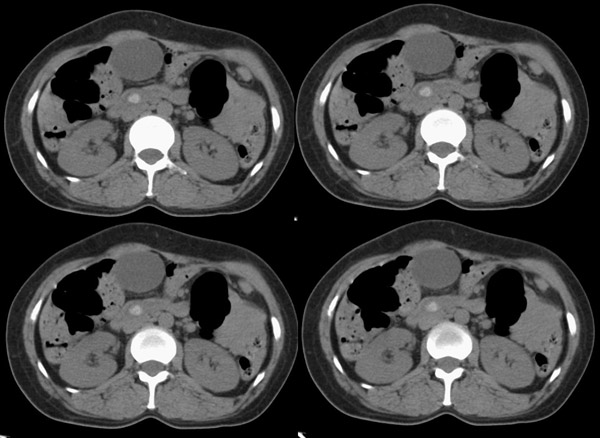

局部1mm薄层重建:

整个胆道系统内可见多发蛔虫钙化改变,胆道扩张.

行胆囊切除术及胆总管探查术:探查见肝脏大小正常,肝缘稍钝,肝表面光整,胆囊大小12*3*3cm3,壁水肿增厚约0。5cm,张力稍高,胆囊与大网膜呈纤维粘连;胆总管宽约2cm,壁明显增厚,触摸胆总管,隐约可触及一条状物,于胆总管做一长约1、5cm的纵行切口,用取石钳在胆总管内取出一条长约16cm长黑色的长条状物,较脆易折断,宽约0、6cm,证实为蛔虫尸体。用探子往下探,未发现下端结石最后诊断:胆道蛔虫症继发胆系梗阻性扩张。